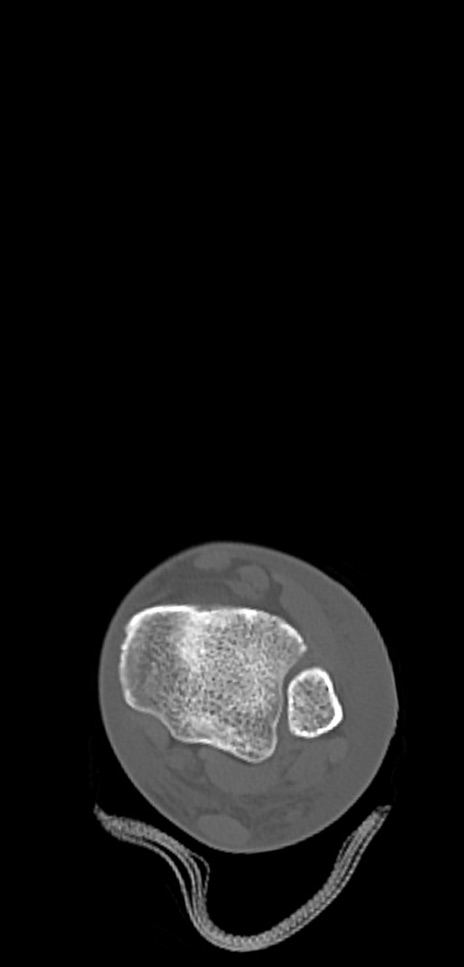

症例37 左足関節CT(横断像)

左足関節CT